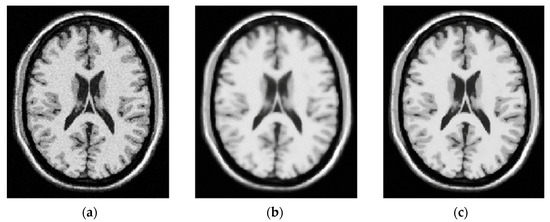

3.1. Step 1 Preprocessing Phase

3.2.1. Initial DA’ Food Sources Extraction Using K-Mean Algorithm